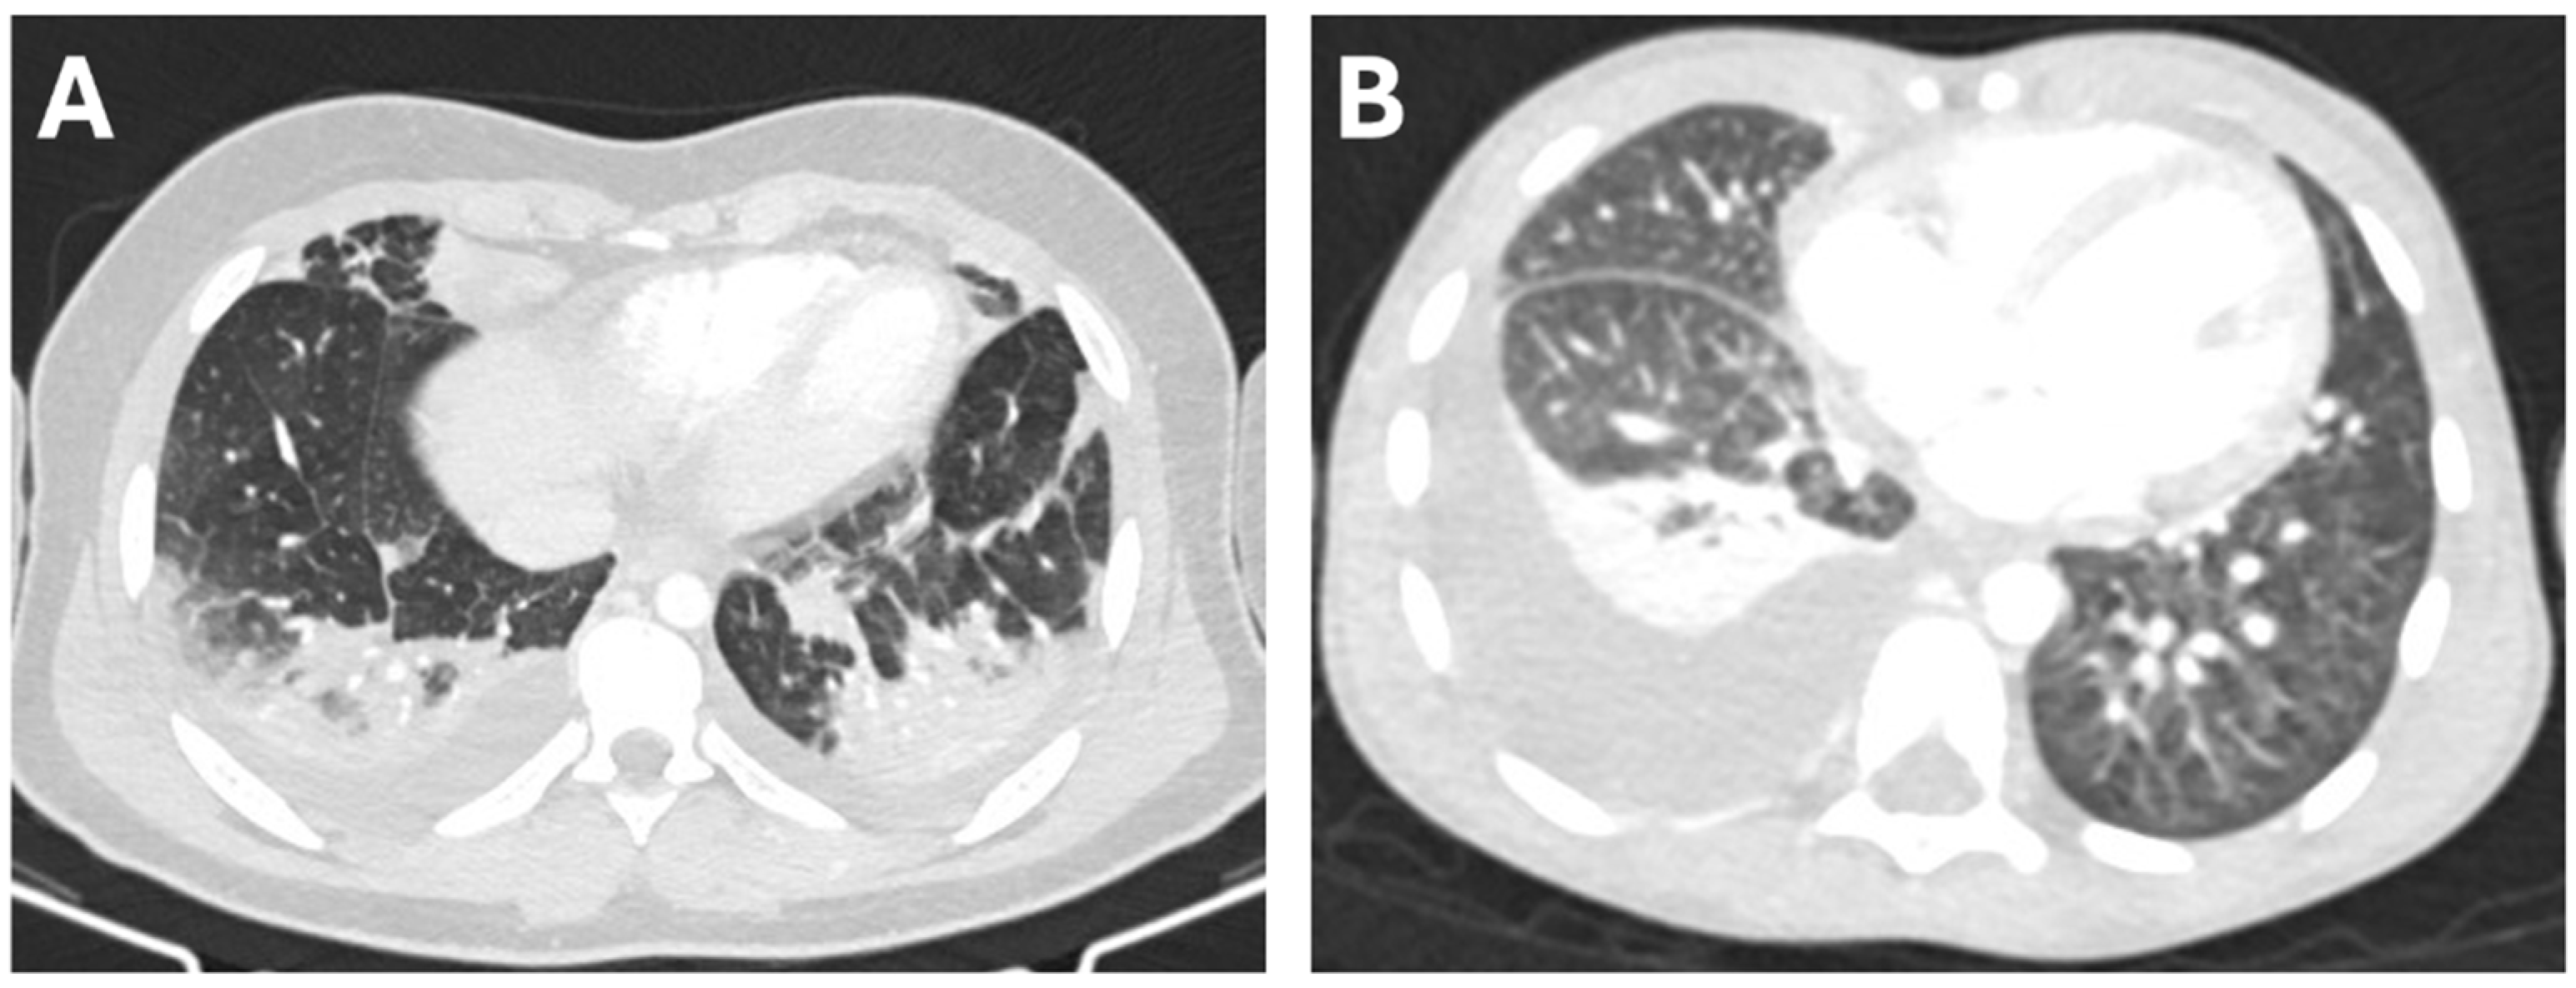

We enrolled 35 patients with pneumonia complicated by pleural effusion, of whom 18 developed PEm, whereas 17 had simple PEf. Chest CT scans from two cases are reported in Figure 1. No differences in gender distribution or age were found between the two groups (Table 1).

Figure 1.

Transverse chest CT scans from a 13-year-old boy with PEf associated with parainfluenza virus pneumonia (A), and from a 5-year-old boy with PEm associated with pneumococcal pneumonia (B).